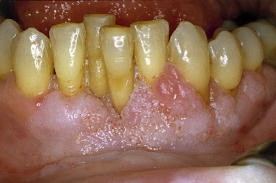

Die proliferative verruköse Leukoplakie (PVL) ist eine seltene Variante der oralen Leukoplakie (OL) mit hoher Transformationstendenz. Sie beginnt als plane Hyperkeratose. Im Verlauf tritt die verruköse Komponente in Erscheinung.

Das klinische Bild der PVL entsprach den in der Literatur beschriebenen Kriterien. Die mittlere Beobachtungsdauer war mit 1,7 Jahren kurz. 3,6 unterschiedliche Lokalisationen von PVL pro Patientin waren zu beobachten. Die Wangenschleimhaut, der zahnlose Alveolarfortsatz und die Gingiva propria waren am häufigsten betroffen. Eine Patientin hatte bereits zum Zeitpunkt der Überweisung ein Karzinom entwickelt. Bei den übrigen Frauen traten im Beobachtungszeitraum Karzinome auf. Unterschiedliche Therapien konnten Rezidive bzw. das Neuauftreten von Zweitkarzinomen nicht verhindern. 2 Patientinnen verstarben an PVL. Histopathologisch ergab sich ein für PVL typisches Spektrum. Homogene plane Leukoplakien zeigen Akanthose, Hyperkeratose und häufig Parakeratose ohne Zeichen einer Epitheldysplasie. Das proliferative verruköse Stadium ist gekennzeichnet durch papillomatöse Epithelveränderungen mit Zeichen geringer Dysplasie des Epithels und subepithelialer Infiltration mit immunkompetenten Zellen. Transformationen führen zu verrukösen Karzinomen oder Plattenepithelkarzinomen.

Proliferative verrucous leukoplakia (PVL) is a rare variant of oral leukoplakia (OL) with a high tendency for malignant transformation. PVL starts as a flat hyperkeratosis. During the course of the disease verrucous lesions develop.

The clinical appearance of PVL was characteristic as compared to criteria described in the literature. The average period of observation in these cases was short (1.7 years). There were 3.6 different localizations observed per patient. The buccal mucosa, gingiva, and edentulous alveolar ridge were most often affected. One patient had already developed squamous cell carcinoma prior to referral. The others developed malignancies during follow-up. Recurrences and secondary malignancies could not be avoided using different therapeutic modalities. Two patients died from PVL. The characteristic spectrum of histopathological findings in PVL was observed. Homogenous flat leukoplakias are characterized by acanthosis, hyperkeratosis, and often parakeratosis. Epithelial dysplasia is not seen. The proliferative verrucous stage of the disease is characterized by papillomatous epithelial growths with signs of slight epithelial dysplasia and subepithelial infiltration with immunocompetent cells. Stages of transformation may result in verrucous carcinoma or squamous cell carcinoma.